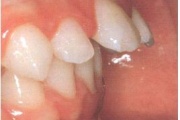

Esimese jäävmolaari ektoopiline lõikumine

Ravijärgne seis. Jäävhammas on täielikult lõikunud.

) Röntgenülesvõte. Ülemise esimese jäävmolaari lõikumine on takistatud 2. piimamolaari tõttu